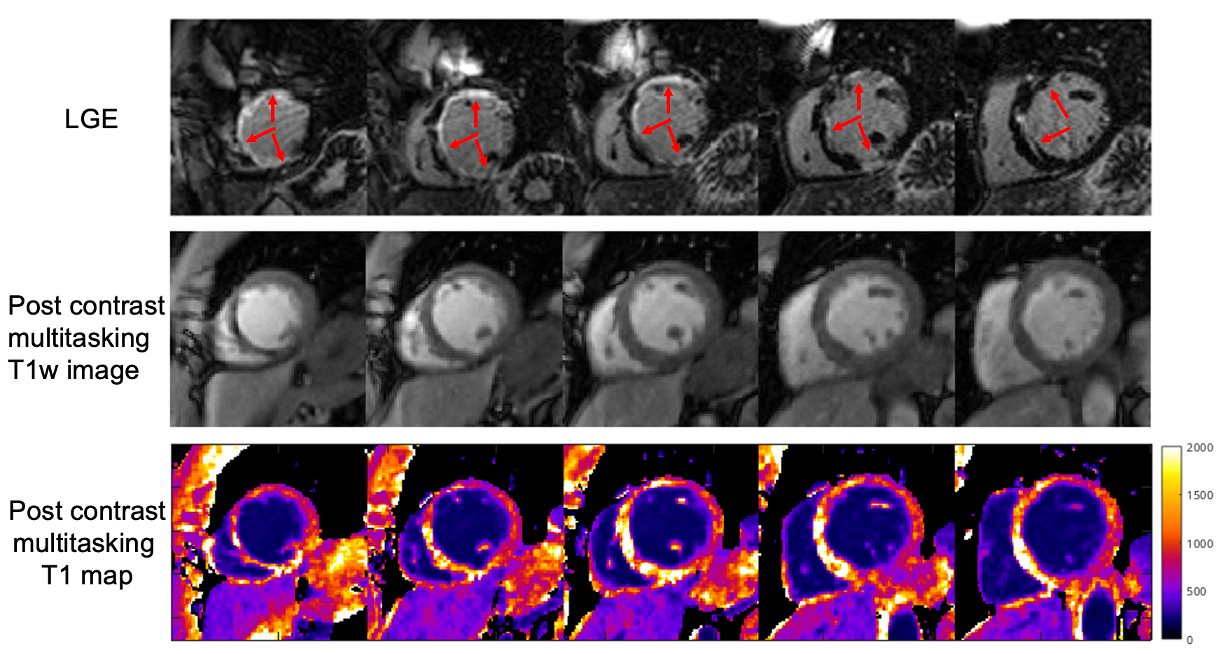

Fig.3. LGE, postcontrast multitasking T1w images and T1 maps of a patient with myocardial scar.